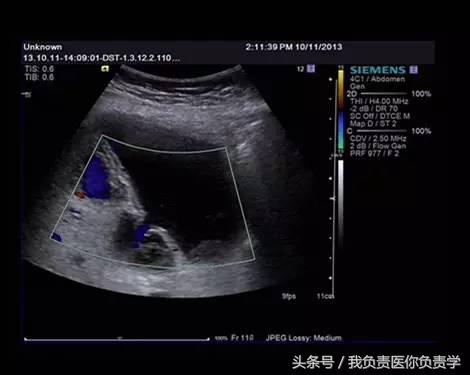

图3-图6示胆囊壁局部回声中断,探头加压及松开时CDFI可见红色及蓝色多普勒信号